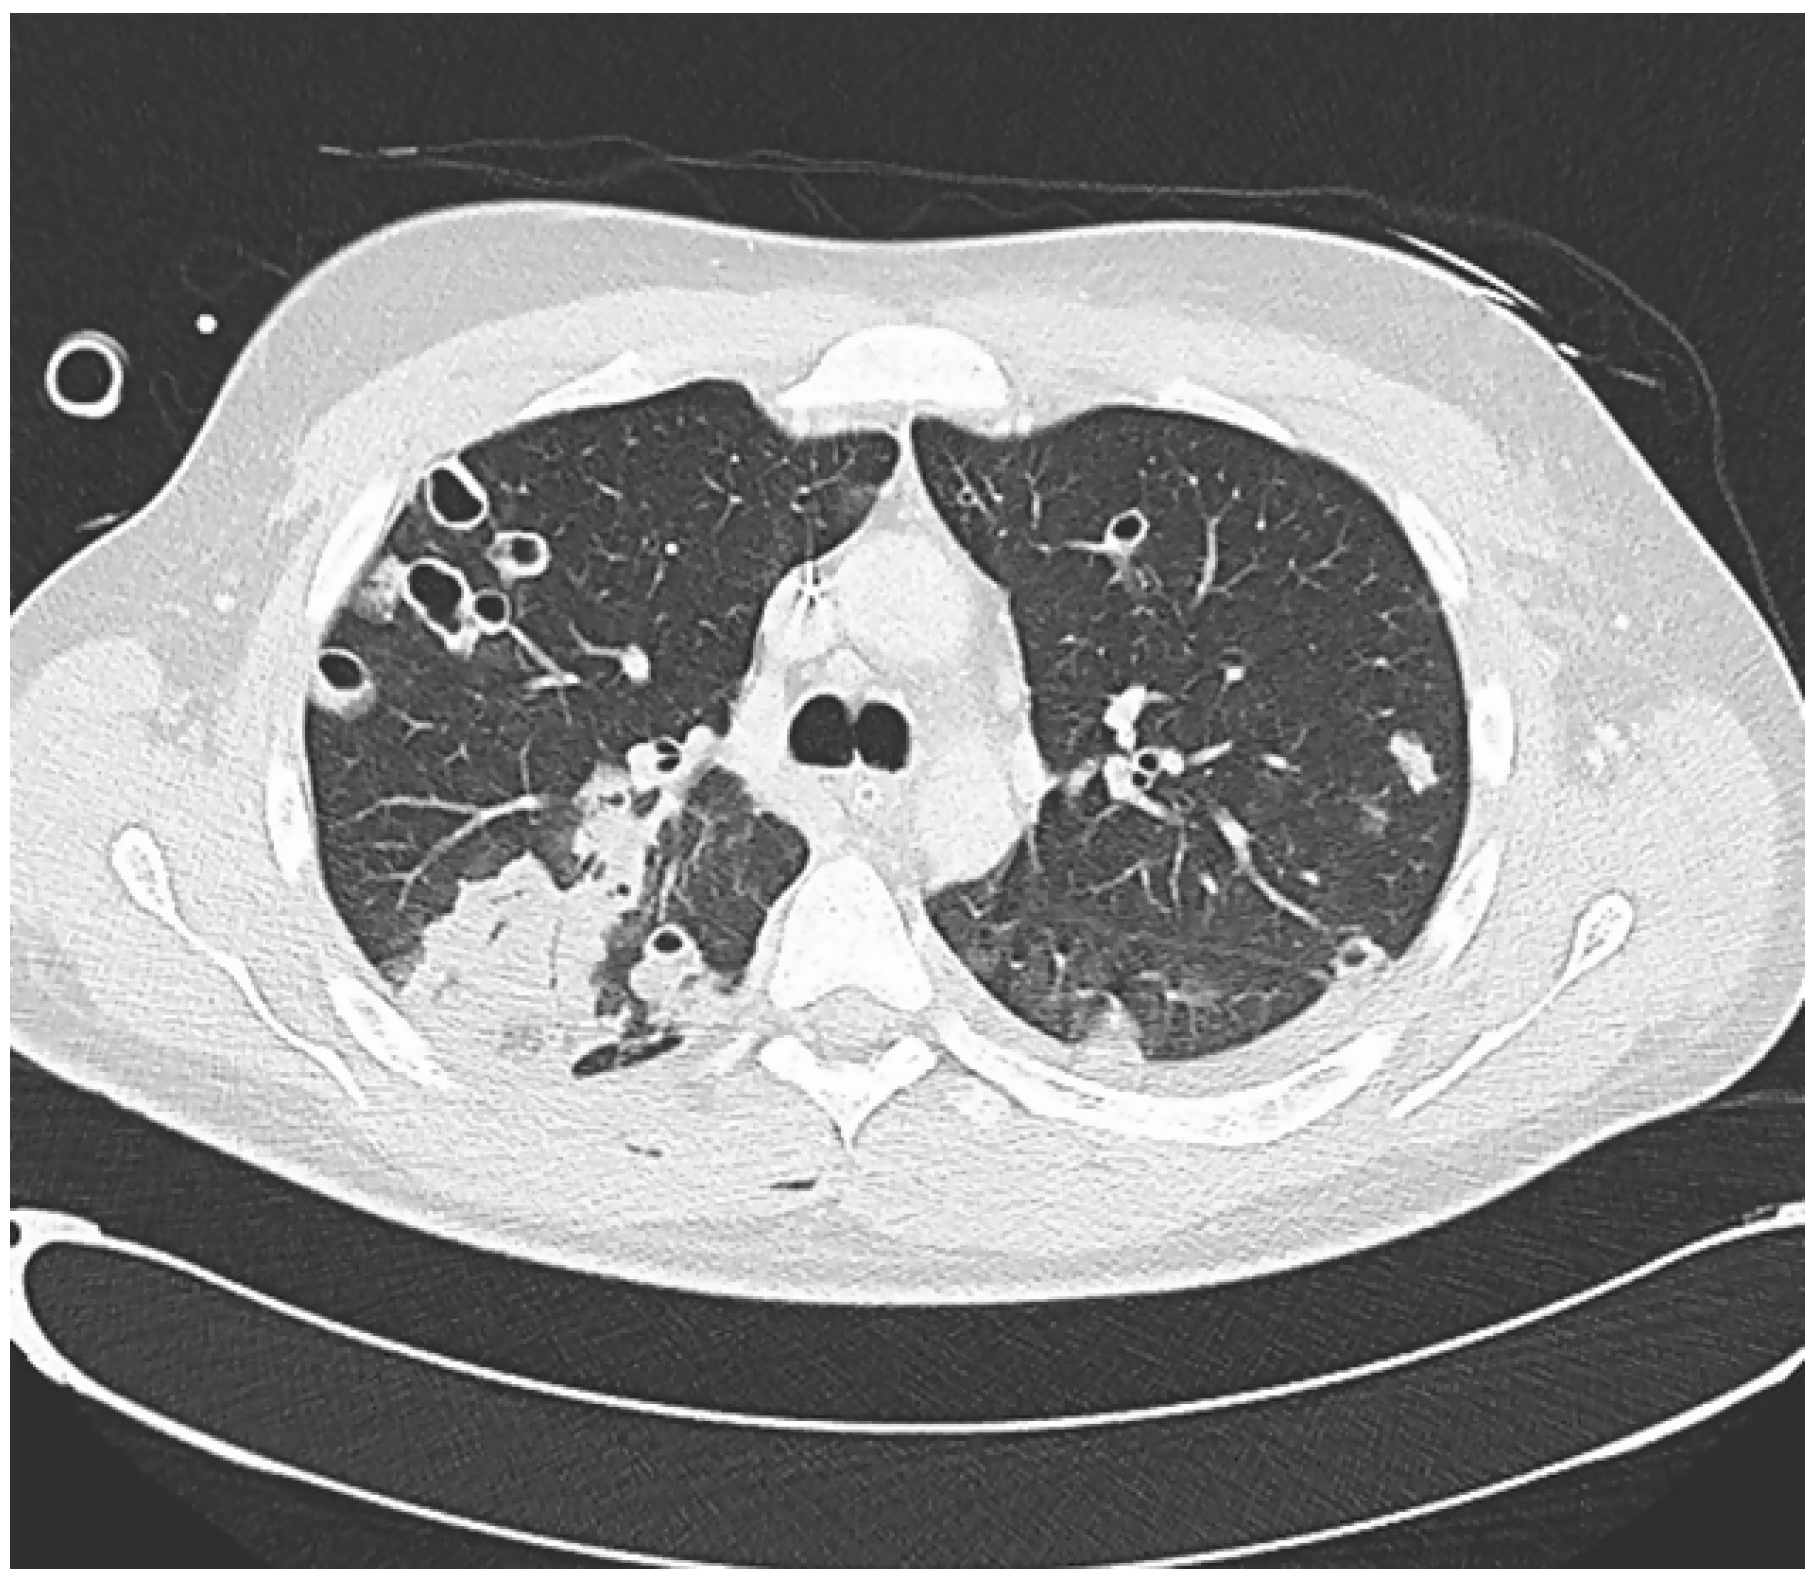

A new physical examination revealed a left cervical bulging (Figure 2) and a contrast-enhanced neck CT scan was carried out, which revealed a thrombus in the left internal and external jugular vein (Figure 3).

Figure 3. Axial view of neck angiotomography showing a filling defect in the internal jugular vein (yellow arrow) and the external jugular vein (white arrow).